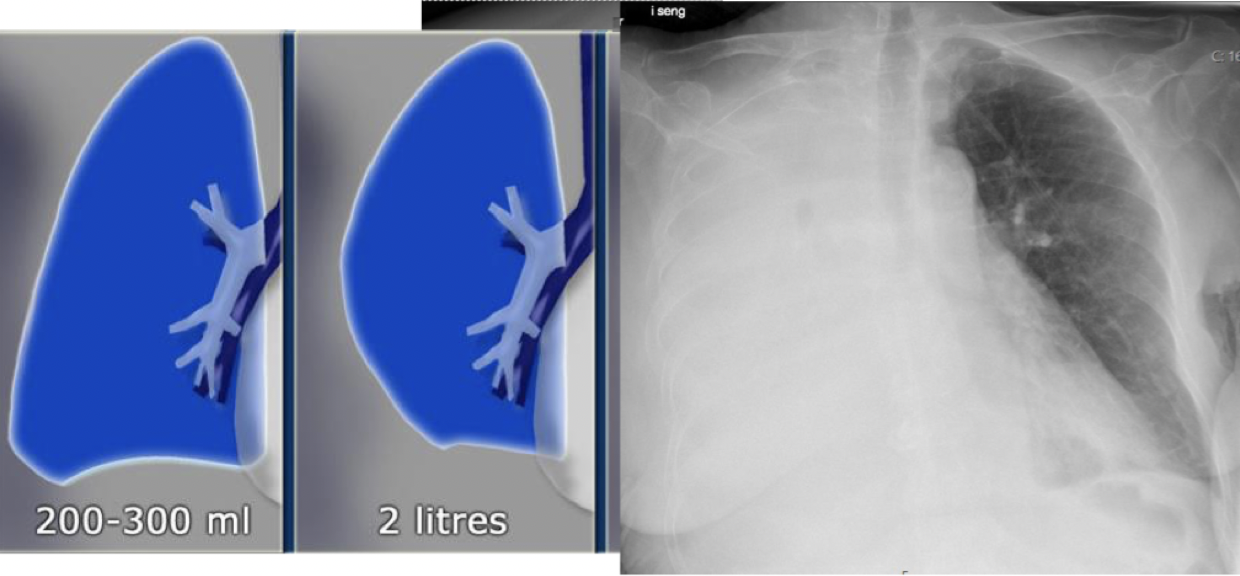

Hva er pleuravæske, og hvordan kan man se dette på rtg. thorax?

A

• Pleuravæske er væske i pleurahulen

- Hjertesvikt - bilateral (på begge sider)

- Infeksjon eller kreft - ensidig

• Pleuravæske samler seg i lungesinus (sinus costodiaphragmaticus) på stående bilde